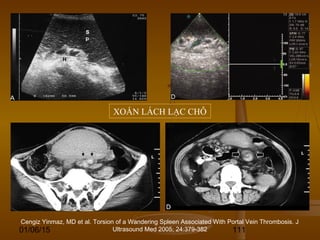

DẤU HIỆU XOÁY NƯỚCDẤU HIỆU XOÁY NƯỚC

(WHIRLPOOL SIGN)(WHIRLPOOL SIGN)

 Hình ảnh giống như xoáyHình ảnh giống như xoáy

nước thấy được trên siêu âm,nước thấy được trên siêu âm,

CT và MRI.CT và MRI.

 Dấu hiệu này thấy ở bệnhDấu hiệu này thấy ở bệnh

nhân bị xoắn các cơ quan như:nhân bị xoắn các cơ quan như:

xoắn tinh hoàn, xoắn u nangxoắn tinh hoàn, xoắn u nang

buồng trứng, xoắn lách lạcbuồng trứng, xoắn lách lạc

chỗ (wandering spleen), xoắnchỗ (wandering spleen), xoắn

ruột ở bệnh nhân xoay ruộtruột ở bệnh nhân xoay ruột

bất toàn (malrotation), xoắnbất toàn (malrotation), xoắn

đại tràng…đại tràng…

XOẮN LÁCH LẠC CHỖ

Cengiz Yinmaz, MD et al. Torsion of a Wandering Spleen Associated With Portal Vein Thrombosis. J

Ultrasound Med 2005; 24:379-382